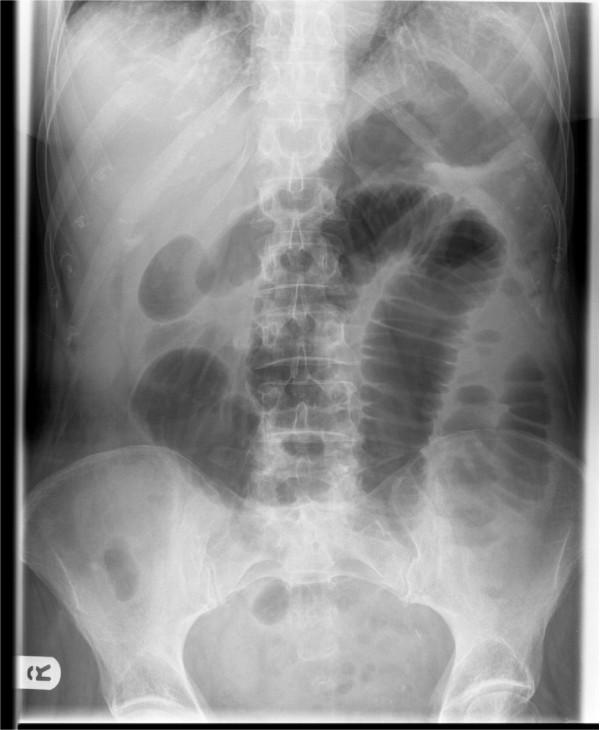

Acute appendicitis is a common surgical problem however the diagnosis is often overlooked when it presents as a small bowel obstruction. In this report we present two cases of elderly patients who presented with small bowel obstruction and raised inflammatory markers. Both patients were successfully treated with a laparotomy, adhesiolysis and appendicectomy and went on to make a good recovery.

急性阑尾炎是常见的外科问题,然而,当它表现为小肠梗阻时,诊断常常被忽视。在本报告中,我们介绍了两例老年患者,他们表现为小肠梗阻且炎症标志物升高。两名患者均通过剖腹手术、粘连松解术和阑尾切除术成功治疗,并顺利康复。